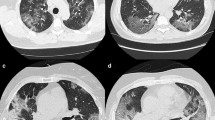

All the chest CTs were analyzed as part of the clinical workflow by senior radiologists from the HCL, including during night shift. The presence of typical features of COVID disease were identified, including ground glass opacity (GGO), crazy paving, sub-pleural bands of consolidations, reversed halo sign, and lung consolidations as described previously [3, 8,9,10,11,12]. An example of these signs is shown in Fig. 1. On the final report, patients were rated as “Surely COVID+” when presenting with peripheral, bilateral, or multifocal GGO of rounded morphology ± consolidation or crazy paving, reversed halo sign, or sub-pleural bands of consolidations. Patients were rated as “Possible COVID+” when presenting with multifocal, diffuse, peripheral, or unilateral GGO ± consolidation lacking a specific distribution and non-rounded or non-peripheral or with only few very small GGO with a non-rounded and non-peripheral distribution or with atypical findings: large pleural effusion, major lymph node size increase, or bronchiolitis pattern. Patients were rated as “COVID−” when the chest CT was normal or demonstrating another pathology.